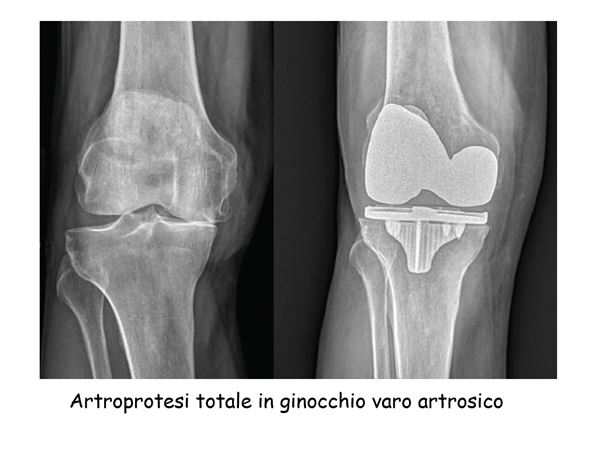

Nell’ambito della mia professione ho approfondito lo studio di tutte le malattie muscolo-scheletriche che insorgono dall’età pediatrica fino all’età senile. Per questo motivo la mia attività chirurgica ha coperto tutti gli ambiti dell’Ortopedia e della Traumatologia, dalla protesica d’anca e di ginocchio (primi impianti e revisioni) alle osteotomie, dalla chirurgia della spalla e del gomito, alla chirurgia del piede (alluce valgo) e della mano (tunnel carpale), prima nel ruolo di Dirigente Medico di I° livello e poi di Direttore della Clinica Ortopedica dell’Adulto e Pediatrica dell’Università Politecnica delle Marche di Ancona.